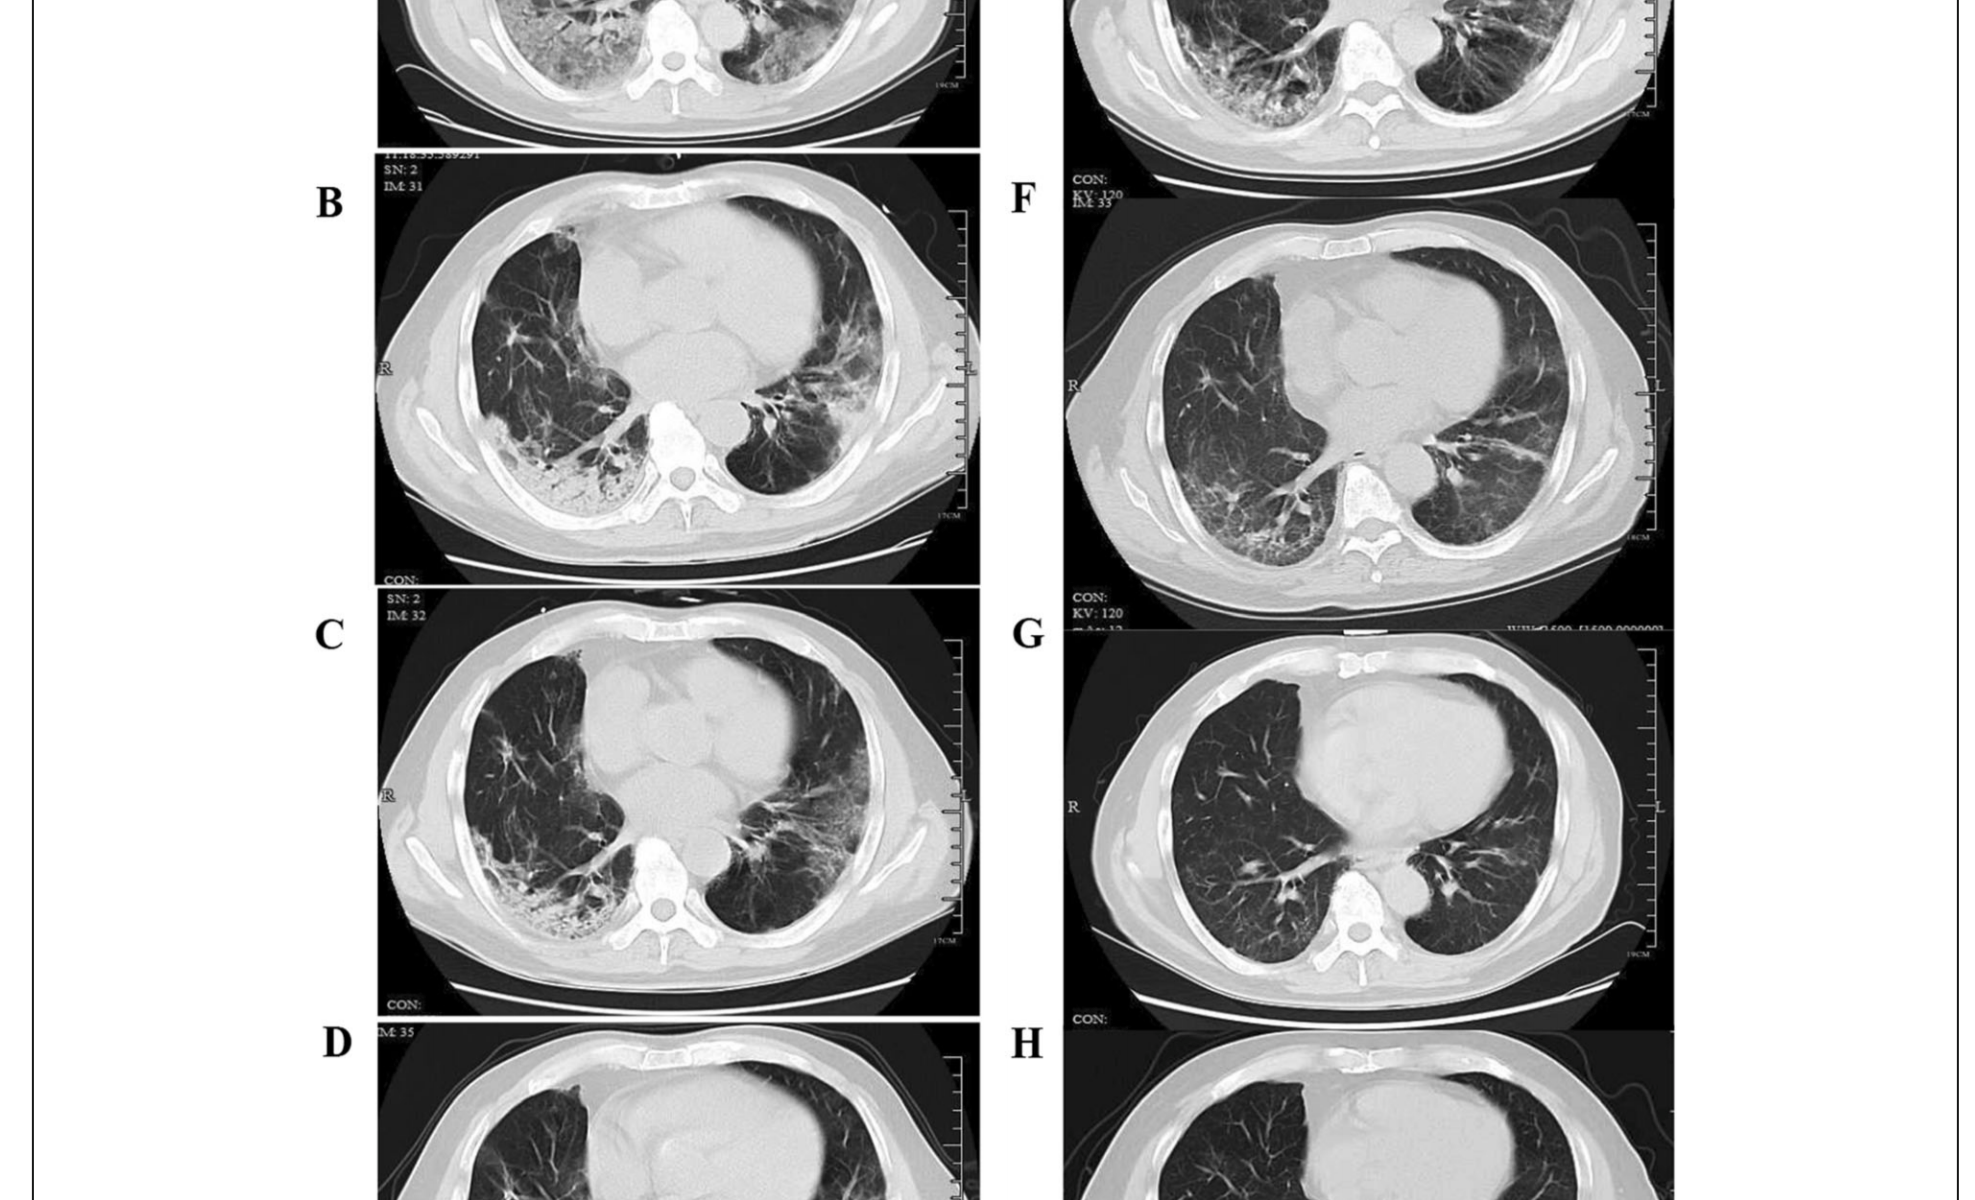

1 Şubat’ta SARS-CoV-2 enfeksiyonu olan, aynı gün hastaneye başvuran ve hastanede yatışı sırasında kortikosteroid ve yüksek akımlı nazal kanül ile oksijen tedavisi verilen hastanın,

A 7. günde elde edilen ve yaygın subplevral GGO’ (buzlu cam opasitesi) yu gösteren bir Tarama.

B Kısmi konsolidasyonlu subplevral GGO’yu gösteren 14. günde elde edilen tarama.

C Hastalığın 21. gününde alınan tarama subplevral GGO ve konsolidasyonun kısmen azaldığını gösteriyor.

D GGO alanlarında gelişen düzensiz lineer opasiteleri gösteren, hastalığın 28. gününde elde edilen tarama.

E Tarama, taburcu olduktan 1 ay sonra (hastalığın 62. günü) düzensiz lineer opasiteler ve subplevral retikülasyon gösteren elde edildi.

F Taburcu olduktan 3 ay sonra (hastalığın 112. günü) alınan subplevral retikülasyon gösteren tarama.

G Taraması taburcu olduktan 6 ay sonra (hastalığın 210. günü) GGO bazında hafif düzensiz lineer opasiteler ve retikülasyon gösteren alanlar elde edilmiştir.

H Tarama, taburcu olduktan 1 yıl sonra (hastalığın 390. günü) ince düzensiz lineer opasiteler ve GGO bazında retikülasyon gösteren tarama.